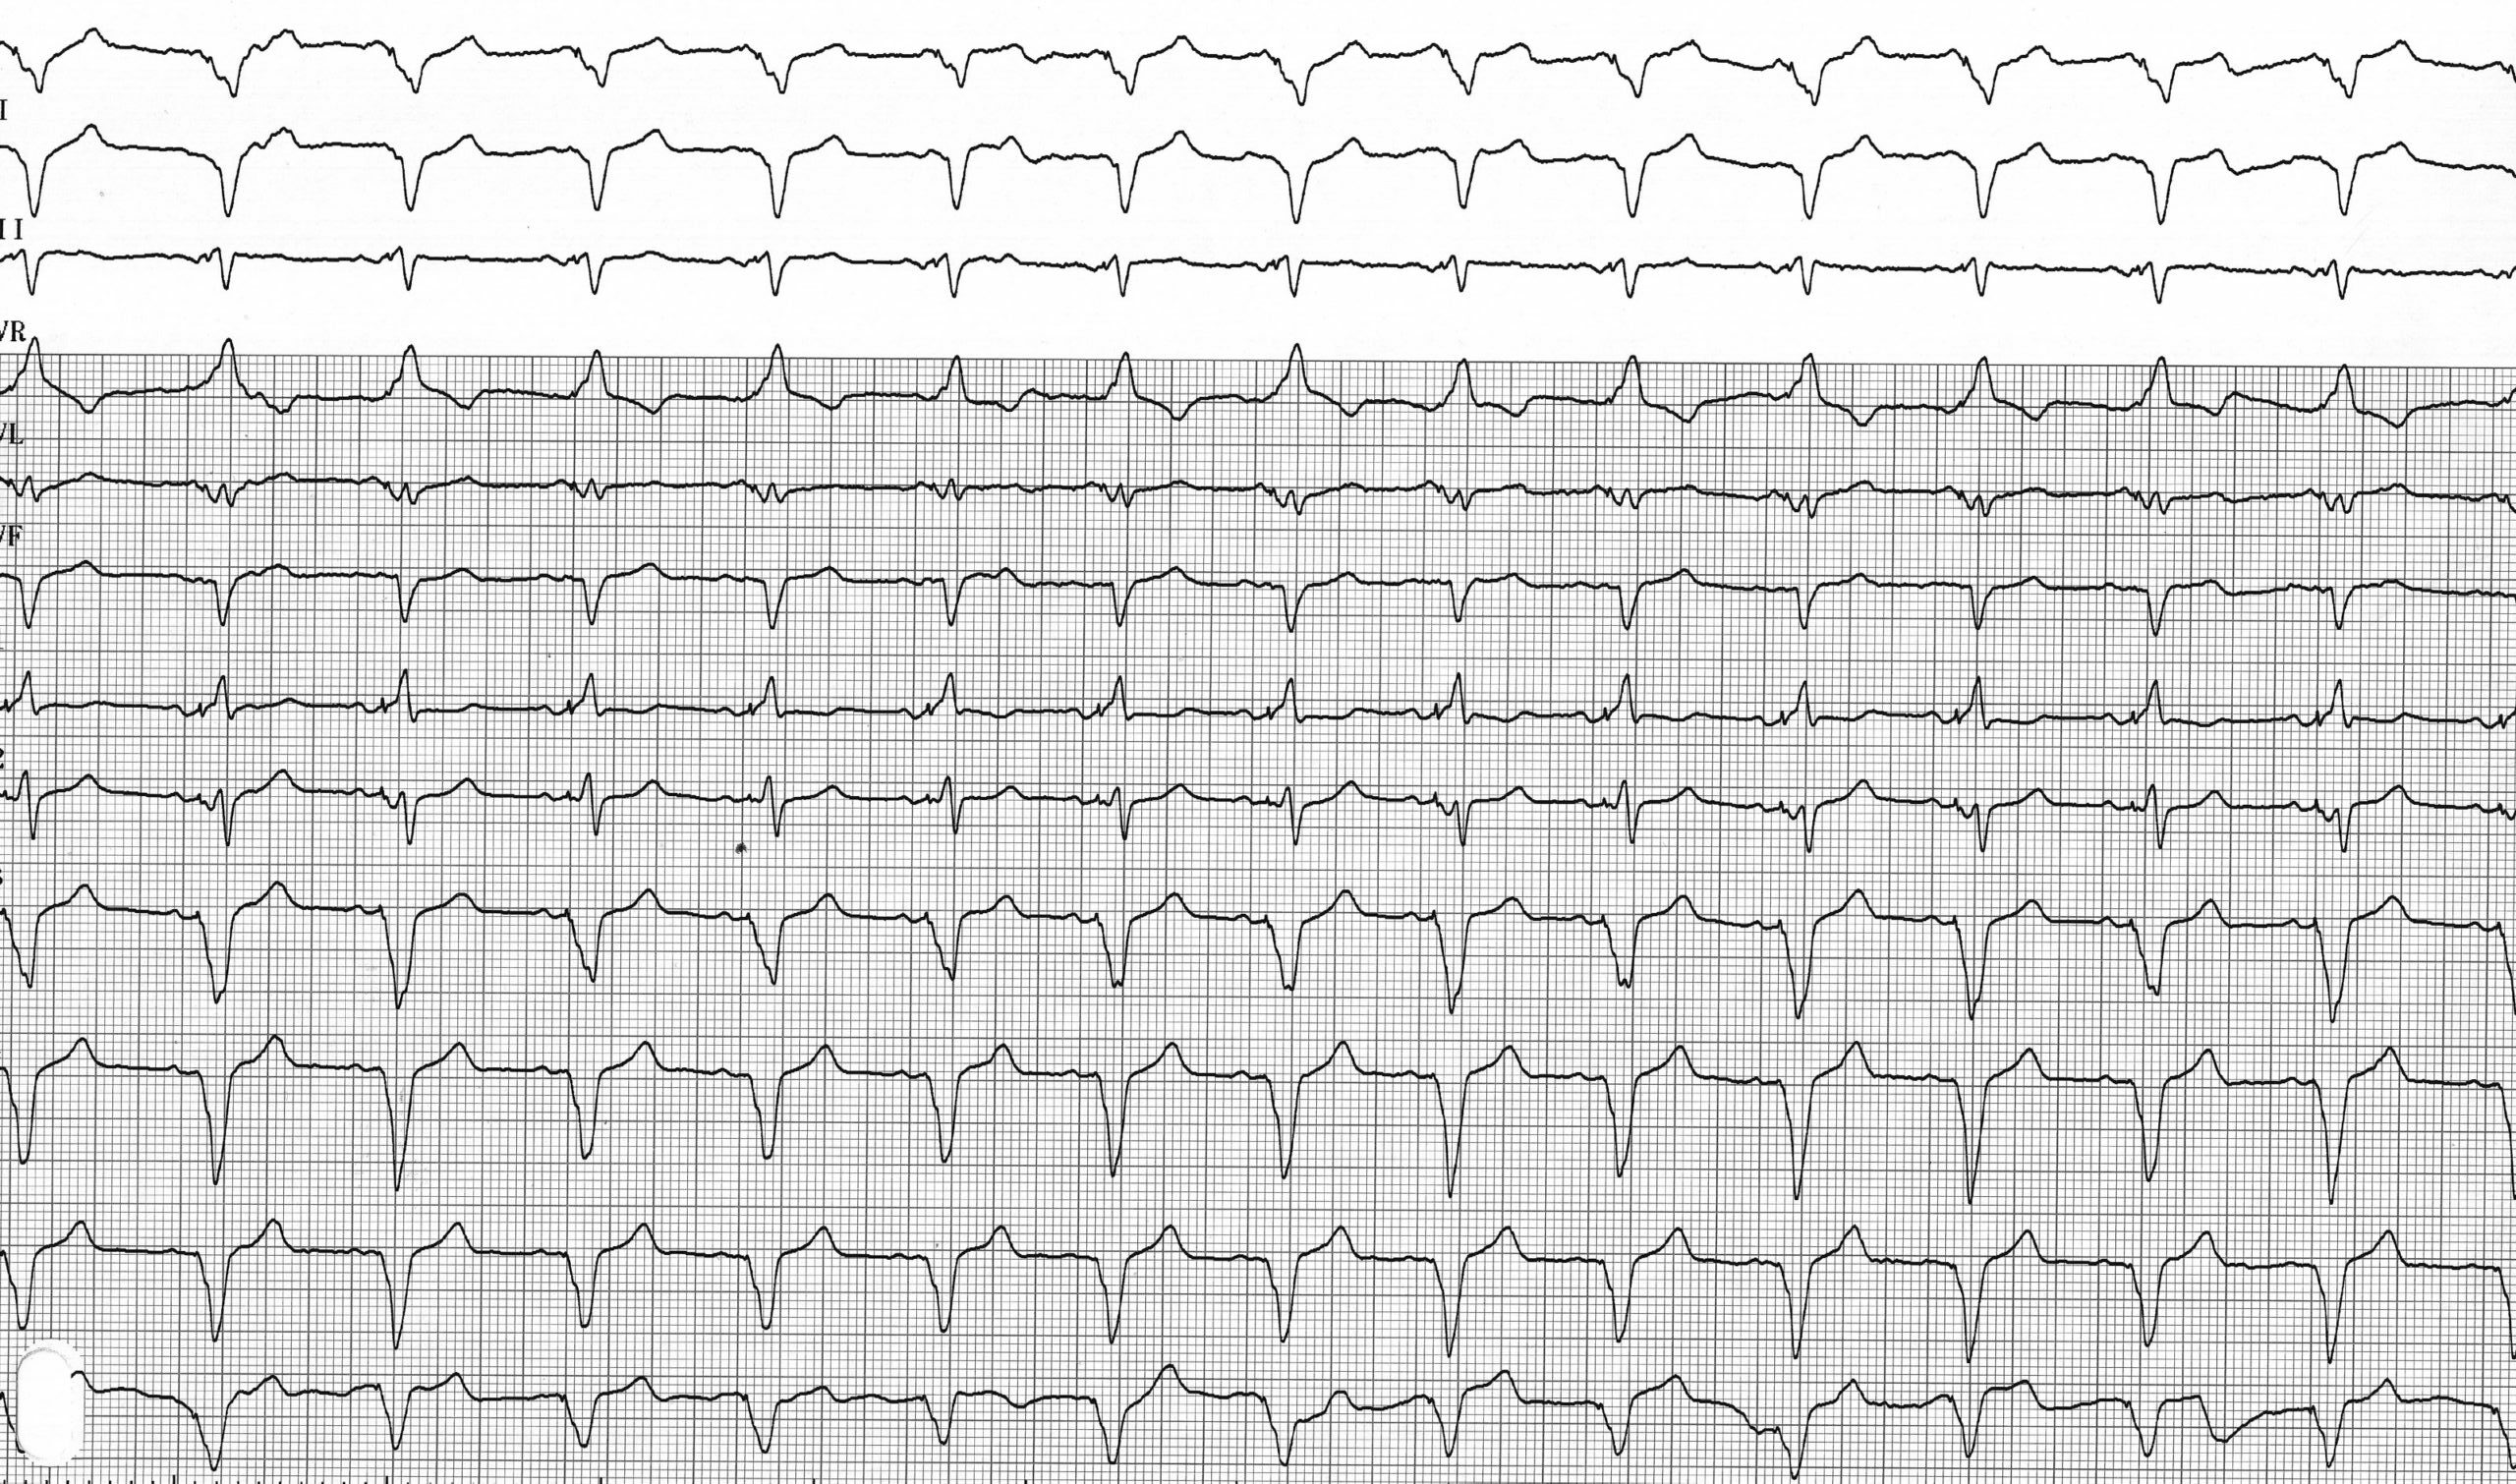

Description tracé

Tracé enregistré après programmation d’une stimulation ventriculaire droite seule; aspect du QRS plus large que lors de la stimulation biventriculaire avec négativité franche dans les dérivations inférieures compatible avec la position apicale de la sonde;